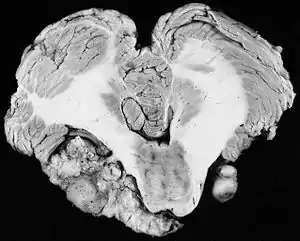

| Bilateral schwannomas in a patient with neurofibromatosis 2 | |

از علائم این بیماری وزوز مداوم گوش و به تدریج کاهش شنوایی و عدم تعادل است. تومورهای زاویه مخچه – پل مغزی فشار به اعصاب جمجمهای مخچه –ساقه مغز و بطن چهارم ایجاد میکنند . فراوانترین علامت در نوروم آکوستیک کاهش شنوایی (در ۸۷٪ بیماران) و وزوز گوش است. شمار کمتری از این بیماران سردرد، سرگیجه و بی حسی صورت دارند. نورم آکوستیک در دهههای ۳تا ۵ شایعتر است. آکوستیک نوروما (AN) در 95 % موارد یک طرفه و حدود 5 % دو طرفه است. نوع دوطرفه آن بسیار نادر رخ می دهد که مرتبط با یک سندرم ارثی به نام نوروفیبرو ماتوزیس نوع دوم (NF2) می باشد. تومور آکوستیک تومور مغزی نیست. این تومور در واقع یک تومور عصب تعادل است و نام علمی تر آن شوانوم وستیبلار می باشد.